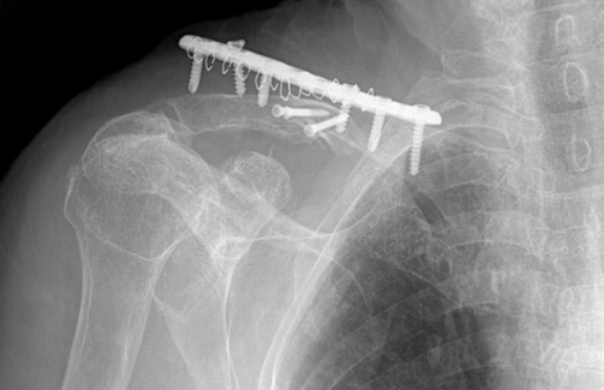

双钢板技术(适用于严重骨质疏松患者)如下图。

-